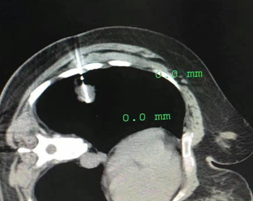

肺部CT專指影像學(xué)名詞——不同于毛玻璃樣改變,指肺部非特異性局灶性小結(jié)節(jié)樣密度增高影。

分為:單純型(略高密度,均質(zhì))、混合型(成分密度不一致,含有實性成分)

病理類型:良性(炎癥、結(jié)核、纖維化、不典型腺瘤樣增生),惡性(早期肺癌, 占檢出的5%~10%)。

1 肺磨玻璃樣病變的特征

發(fā)展非常緩慢,以年計算——發(fā)現(xiàn)了也別慌

發(fā)展結(jié)局多種多樣——大多數(shù)不是癌

小磨玻璃樣結(jié)節(jié)惡變風(fēng)險很低(<5mm, 0.9%)

2 肺磨玻璃病變——何時需要盡早治療?診斷或高度懷疑為肺癌

大多數(shù)的肺磨玻璃樣結(jié)節(jié)都是良性,不需要處理;>8mm惡性磨玻璃樣結(jié)節(jié)只占5%~10%

懷疑肺癌的肺磨玻璃樣結(jié)節(jié)的特征:

不明原因新近出現(xiàn),并持續(xù)存在半年以上

單發(fā),含有實性成分,尤其實性部分超過50%

進行性增大、大小超過2cm

具有肺癌影像表現(xiàn):毛刺征、空泡征、結(jié)節(jié)內(nèi)支氣管征